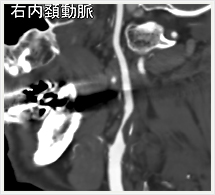

画像紹介(頭頚部血管編)

画像は、頚動脈の狭窄部分に“ステント”と呼ばれる金属性の網状の筒を留置して、血管を正常径まで拡張させる手術です。この治療は、内膜剥離術と比較して非侵襲的であり、高齢者やいろいろな合併症を持った方にも負担を少なくして行うことができます。術後の安静期間や入院期間も短いのが特徴です。